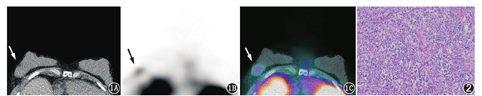

为鉴别该肿块的良恶性,患者于本科行99Tcm-甲氧基异丁基异腈(methoxyisobutylisonitrile, MIBI)SPECT/CT显像,于左侧肘静脉注射99Tcm-MIBI(上海欣科医药有限公司苏州分公司提供,放化纯>95%)111 MBq后,分别于注射后20 min及2 h取俯卧位行胸部SPECT/CT(荷兰Philips公司Precedence)断层采集。早期显像(图1)示双侧乳腺腺体致密,右乳外上象限见一大小3.0 cm×2.8 cm软组织肿块影,与周围乳腺组织分界欠清,密度较均匀,未见钙化,边缘无毛刺;该病灶放射性摄取高于周围正常乳腺组织,肿瘤/正常乳腺组织放射性值(tumor/non-tumor, T/NT)为3.9;2 h延迟显像示该病灶放射性摄取减低,但仍高于周围正常乳腺组织,T/NT为2.6,考虑该病灶为恶性病变的可能性大。

显像2 d后患者在全身麻醉下行右乳肿块切除术,完整切除肿块,术中送快速病理提示右乳恶性肿瘤;标记肿块上下内外切缘,快速病理示切缘阴性。术后巨检:乳腺组织1块,体积3.0 cm×2.8 cm×2.5 cm,中央见球形肿块1个,直径约2.5 cm,切面暗红质嫩,无包膜。光学显微镜检查结果(图2)示肿瘤细胞弥漫性分布,体积较大,细胞核有异型,可见核仁。免疫组织化学检查:人表皮生长因子受体2(human epidermal growth factor receptor-2, HER2;-)、雌激素(estrogen, ER;-)、孕激素(progesterone, PR;-)、细胞增殖核抗原Ki-67 (60%+)、细胞角蛋白(cytokeratin, CK)14(-)、P63(-)、CD38(-)、CD3(部分+)、CD79a(+)、CD43(-)、CD138(-)、CD20(+)、CD56(小灶性+)、P120(-)、多发性骨髓瘤癌基因蛋白(multiple myelomaoncogene 1,MUM1;+)。病理诊断为右乳恶性淋巴瘤,弥漫大B细胞性。

本例患者为致密型乳腺,钼靶X线灵敏度低,SPECT/CT显像中CT图像示病灶与周围正常乳腺组织分界欠清,且密度相近(图1A),因此单纯的CT图像对其诊断较为困难;而99Tcm-MIBI显像示病灶处可见放射性高摄取(图1B),正常乳腺组织则未见明显放射性摄取,从而有助于诊断。马庆杰等[5]的研究表明,99Tcm-MIBI在乳腺癌中T/NT为2.26±0.99,本例病灶早期及延迟显像T/NT分别为3.9和2.6,其T/NT略高于乳腺癌。由于PBL少见,目前关于PBL的99Tcm-MIBI显像的相关报道较少,其T/NT尚未见大量报道,有望将来收集更多的病例进一步研究。